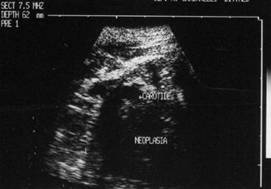

Carcinom anaplaZiC (recidiva)

Lob drept, proiectie trasversala si longitudinala

Barbat de 65 ani. Recidiva voluminoasa

laterocervical dreapta dupa un neoplasm anaplazic cu celule fuzate; tratament -

chimioterapie si radioterapia. Carotida dreapta inglobata si infiltrata

Femeie de 56 ani. Carcinom anaplazic de 34x56 mm in lobul

drept al tiroidei.

Tratament chirurgical urmat de chimio si radioterapie.

Femeie de 44 ani. Formatiune nodulara voluminoasa a lobului drept, cu crestere rapida, de

consistenta dura.

Margini difuze, structura neomogena cu arii hipoecogene si altele ecogene. Examen

citologic prin citoaspiratie: carcinom anaplazic. Examen histologic

postoperator: carcinom anaplazic cu aspect insular.

Aceeasi pacienta - vascularizatie minuma in interiorul nodulului, probabil datorita fenomenelor necrotice.